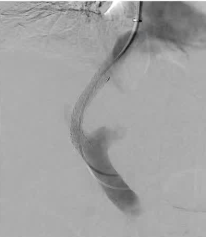

* 需要预防性抗生素 在介入放射学(IR)中,预防性使用抗生素的做法十分普遍;然而,这种做法是基于外科文献中的数据。尽管已发布的指南有助于确定接受经皮操作的患者是否需要预防性使用抗生素,但当地的实际操作模式往往决定了何时使用此类药物。Khurana 2022 介绍了在常见的 IR 操作(即饲食管和导管置入)中围手术期抗生素使用的现状。 清洁 Clean Class I ![]() ![]() ![]() ![]() 污染切口 contaminated Dirty ![]() ![]() 1. 预防(无菌条件)>> 预防性治疗(抗生素)>> 治疗(抗生素、引流……) 2. 预防性使用抗生素的时机影响重大:术前应用可使总体感染率降低约一半,与术后 30 分钟给药相比;术前 30 分钟给药比更早给药感染更少(例外:万古霉素、氟喹诺酮类) 半衰期可能会影响预防用药的持续时间 3. 单次短程预防用药往往与完整的 5 天抗生素疗程效果相当 4. 合理选择抗生素可减少滥用和不良副作用